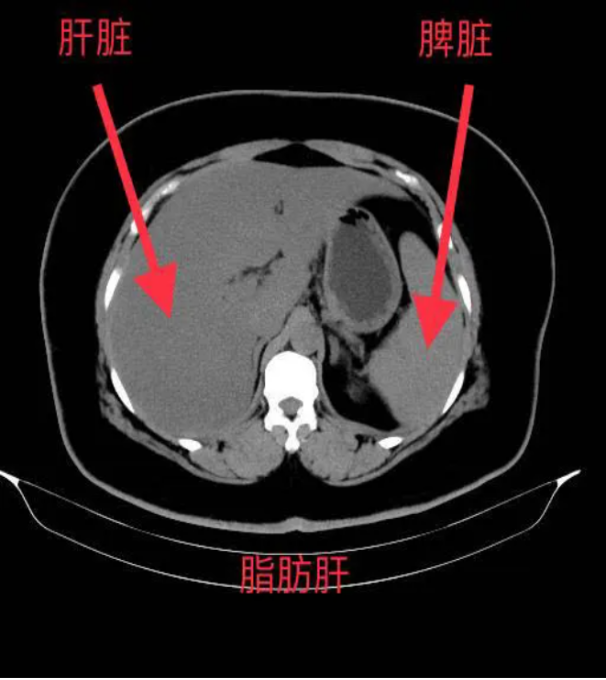

CT(计算机断层扫描)是利用X射线对人体进行断层扫描,并通过计算机重建图像的检查方法。对于脂肪肝的诊断,CT可以提供以下信息:

*肝脏密度降低:脂肪的CT值低于正常肝组织,因此脂肪肝在CT图像上表现为肝脏密度普遍降低,与脾脏密度相比更加明显。

*肝内血管模糊:由于脂肪的堆积,肝内血管在CT图像上会变得模糊不清,甚至消失。

*肝脾CT值比值:正常情况下,肝脏CT值高于脾脏,而脂肪肝患者的肝脾CT值比值会降低,甚至出现反转。